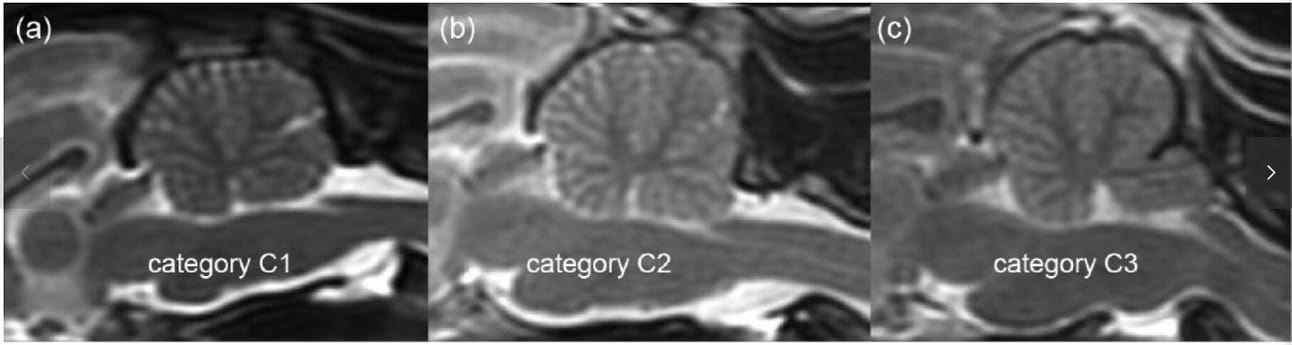

Representative sagittal T2-weighted images of the three cerebellar shape categories: (a) convex caudal surface and rounded caudoventral margin (category C1); (b) flattened caudal surface with caudoventral margin showing a blunt right angle (category C2); and (c) concave caudal surface with cerebellar vermis entering into or herniating through the foramen magnum (category C3)

Forty percent of the cats displayed cerebellar crowding or herniation (category C3) without neurological signs. Persian cats showed a significantly higher prevalence of this morphology compared to several other breeds, suggesting a link with brachycephalic conformation. However, no significant correlation was found between occipital bone shape and cerebellar shape. Cats with higher ICCR, indicative of brachycephaly, were more likely to show cerebellar herniation. Occipital bone thickness varied across the population but did not correlate with breed or cerebellar morphology.